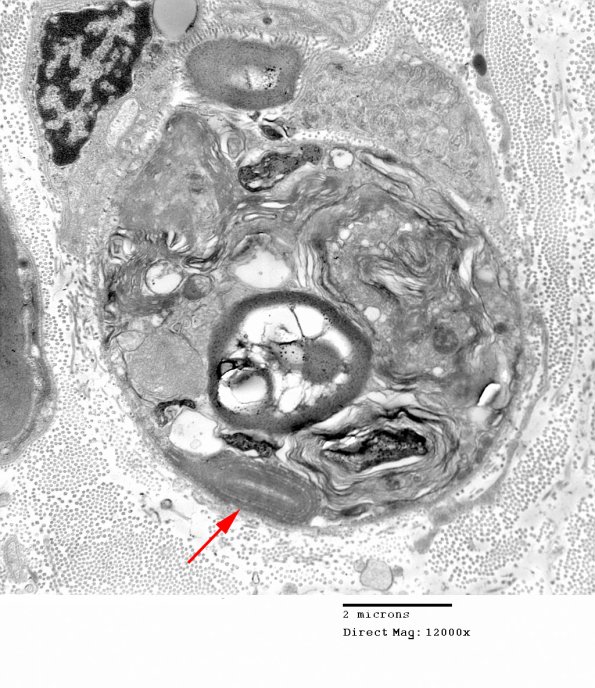

In this case large pieces of the compact myelin sheath are common. The larger fragments in some cases resemble artifactual changes produced by biopsy-induced crush injury. Small fragments of myelin (arrow) and axonal debris are more consistently seen in genuine axonal degeneration.